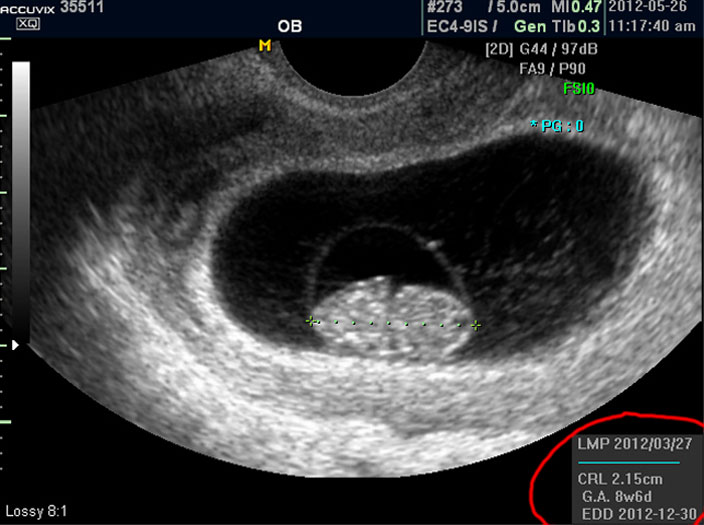

우선 첫번째로 보이는 사진에서 가운데 하얗게 보이는 것이 태아입니다.

우측이 머리 부분이고 좌측이 몸통 부분이며 초기 임신에서는 아기 머리가 몸통의 반정도로 상당히 큰 상태입니다.

따라서 하얗게 보이는 태아 주변의 검은 부분은 양수입니다.

태아의 크기는 우측 하단에 실제 크기가 나와 있지만 아래 사진에서 빨갛게 표시한 부분의 안에 보이는 눈금이 1cm입니다.

마지막으로 볼 것은 아기의 정보를 나타내 주는 수치들입니다.

으로 우측의 LMP라고 된 숫자는 산모의 최종 월경일이며 이는 초음파로 판단한 것이 아니라 산모의 진술을 바탕으로 한 것인데 이것이 중요한 이유는 초음파는 그저 크기만을 알아 내는 것이라 임신 주수에 걸맞게 잘 자라는지 판단하려면 월경 주기를 알아야 하기 때문입니다.

그 아래 보이는 CRL이라는 것은 Crown Rump Length의 약자로 아기의 머리부터 엉덩이 끝까지의 실제 길이입니다.

임신 12주 내지 13주 정도의 초반기의 아기 발육은 주로 아기의 전체 크기를 가지고 판단하는데 엉덩이까지 체크하는 이유는 흔히 태아는 다리를 구부리고 있기 때문에 성인 인간처럼 머리끝부터 발끝까지 실제 키를 재기가 어렵기 때문입니다.

그 아래 GA 는 Gestational Age의 약자로 우리말로는 태령이라고 하며 초음파의 CRL을 기준으로 했을 때 어느 시기의 태아의 수준인가를 말해 주는 것입니다.

따라서 산모의 LMP를 기준으로 한 태령과 초음파로 측정한 태아의 태령은 1주 정도의 오차로 비슷한 것이 정상이며 간혹 최종 월경일을 틀리게 알고 있거나 아기의 발육에 문제가 있을 때는 큰 차이가 날 수 있습니다.

맨 아래의 EDD는 Estimated Due Date의 약자로 출산 예정일을 말하는데 초음파를 기준으로 했을 때 이정도 시기가 출산 예정일이 될 것이라는 계산입니다.

그러나 이것은 어디까지나 초음파로 예상한 시기이며 실제 출산은 앞뒤로 2주 씩의 오차가 있을 수 있습니다.